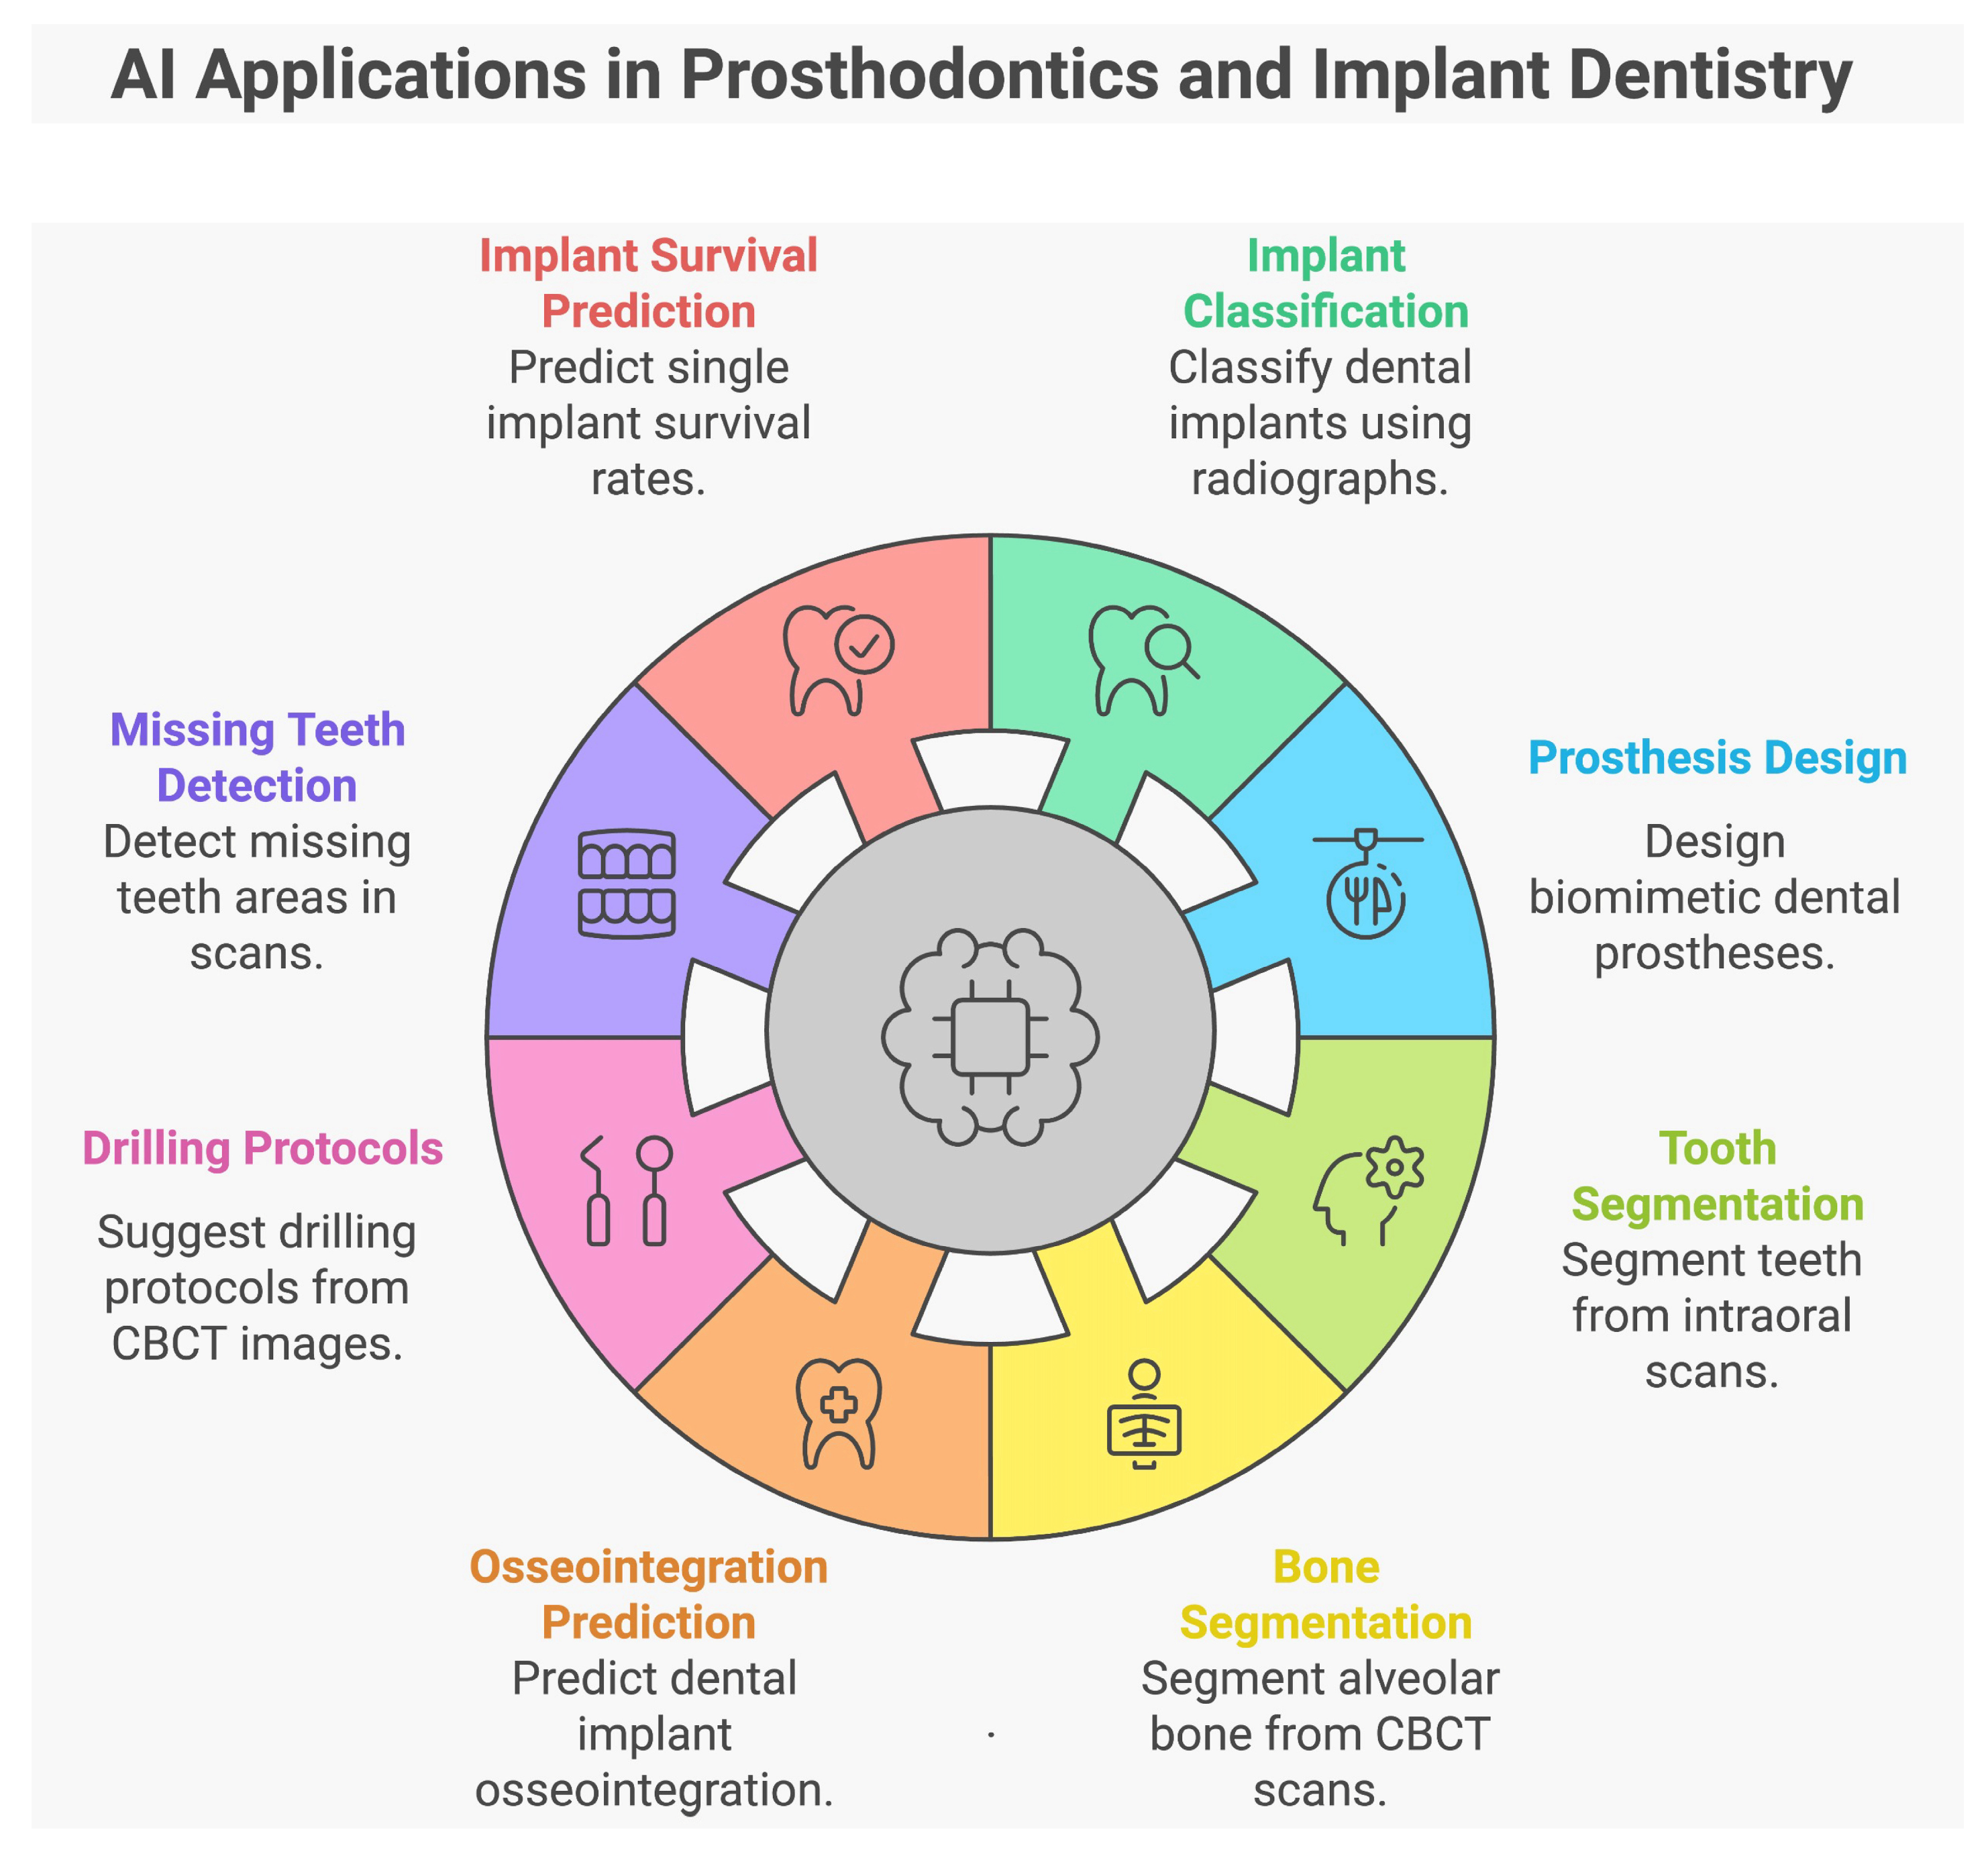

2. Materials and Methods

3. Results

3.1. Applications of AI in Prosthodontics and Implant Dentistry

3.1.1. Characteristics of the Included Studies